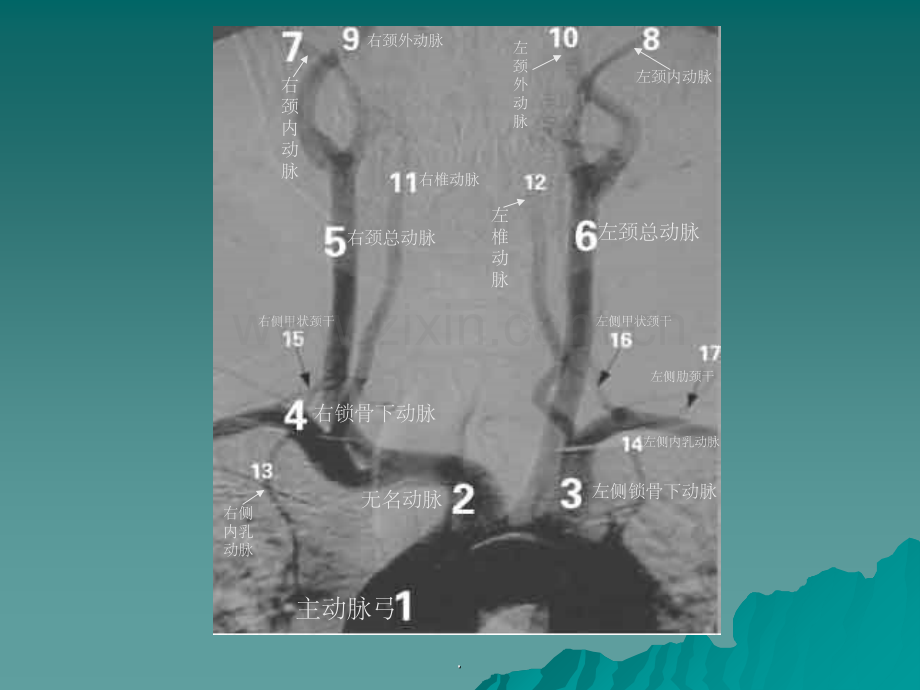

正常主动脉弓及其分支正常主动脉弓及其分支.主动脉弓 无名动脉 左侧锁骨下动脉 右锁骨下动脉右颈总动脉左颈总动脉右颈内动脉左颈内动脉右颈外动脉左颈外动脉右椎动脉左椎动脉右侧内乳动脉左侧内乳动脉右侧甲状颈干左侧甲状颈干 左侧肋颈干.